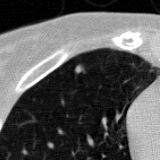

The current study focuses on lung nodule retrieval from a database of CT scans, where patches taken from CT slices of pulmonary nodules are to be mapped into an embedding. LIDC-IDRI [5] is a dataset of thoracic CT scans of 1,010 patients. All the scans were annotated by up to four radiologists, where each one identified, segmented and evaluated separately the lung nodules of a diameter above . Their evaluation also included ratings for a set of 9 characteristics: Subtlety, Internal structure, Calcification, Sphericity, Margin, Lobulation, Spiculation, Texture and Malignancy. The rating system was based on a discrete score of 1-5. Four examples of nodule patches are illustrated in Figure 2: 2 benign (a, b) and 2 malignant (c, d). A rounded vector of the mean rating is bellow each nodule, with the characteristics ordered according to the listing above. The most prominent difference between a and b is the calcification: 3 (solid) and 6 (absent) accordingly. d compared to c has a more defined margin, is more lobulated, but less spiculated. The malignancy score is used to define malignancy classes: score of 1-2 is benign, score of 3 is unknown, and a score of 4-5 is malignant.

(a) Benign

3, 1, 3, 3, 4, 3, 1, 5, 1

(b) Benign

3, 1, 6, 5, 5, 1, 1, 5, 2

(c) Malignant

5, 1, 6, 3, 3, 4, 1, 5, 5

(d) Malignant

4, 1, 6, 3, 4, 2, 2, 5, 4